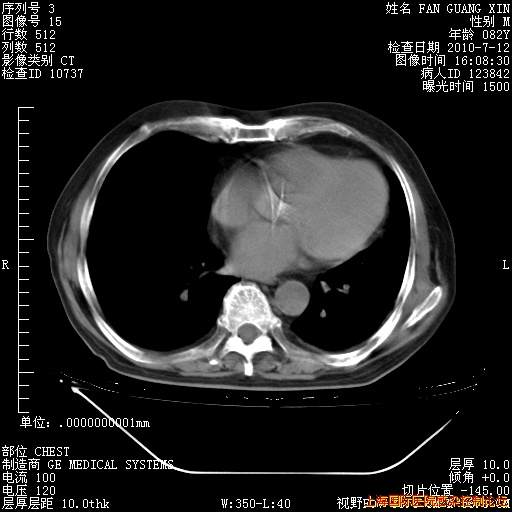

今天复查CT

今天CT

整整相隔30天的肺部CT好像有所好转啊。甲强龙减量第3天,需要观察体温。